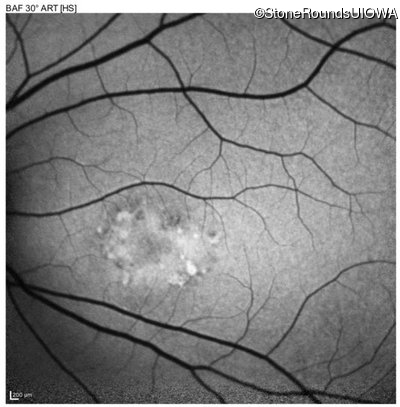

AR Stargardt Disease (IIA)

Age at visit: 20 years

Age at visit: 22 years

AR Stargardt Disease ABCA4 Gly607Arg GGG>AGG Gly1961Glu GGA>GAA AR